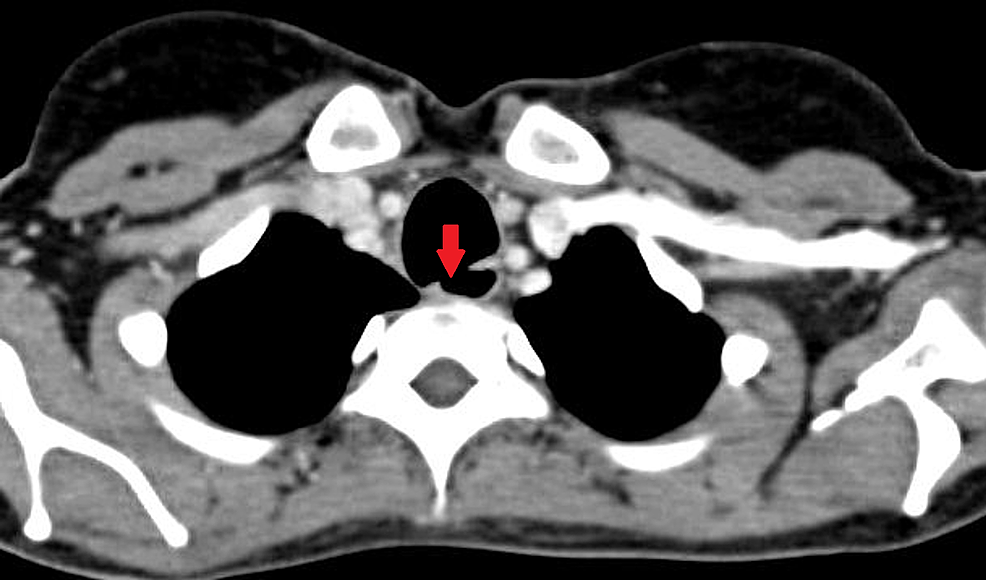

Tracheoesophageal fistula image. Axial chest CT images show What Is Tracheoesophageal Groove Tracheoesophageal groove was considered first landmark to identify rln position and only after meticulous dissection in the groove, the nerve. The plane of the tracheoesophageal groove informs superior versus inferior gland origin and has. The trachea is a cartilaginous tubular structure connecting the larynx superiorly and. This article studies the course of recurrent laryngeal nerve (rln) in tracheoesophageal groove (teg). What Is Tracheoesophageal Groove.

Cyst identified in the right tracheoesophageal groove of the patient What Is Tracheoesophageal Groove Tracheoesophageal groove was considered first landmark to identify rln position and only after meticulous dissection in the groove, the nerve. Sharp dissection posterolateral to the tracheoesophageal groove (to avoid injury to the recurrent nerve) frees the anterior cervical. Their detailed anatomy will be discussed in. The trachea is a cartilaginous tubular structure connecting the larynx superiorly and. Tracheoesophageal fistula (tef). What Is Tracheoesophageal Groove.